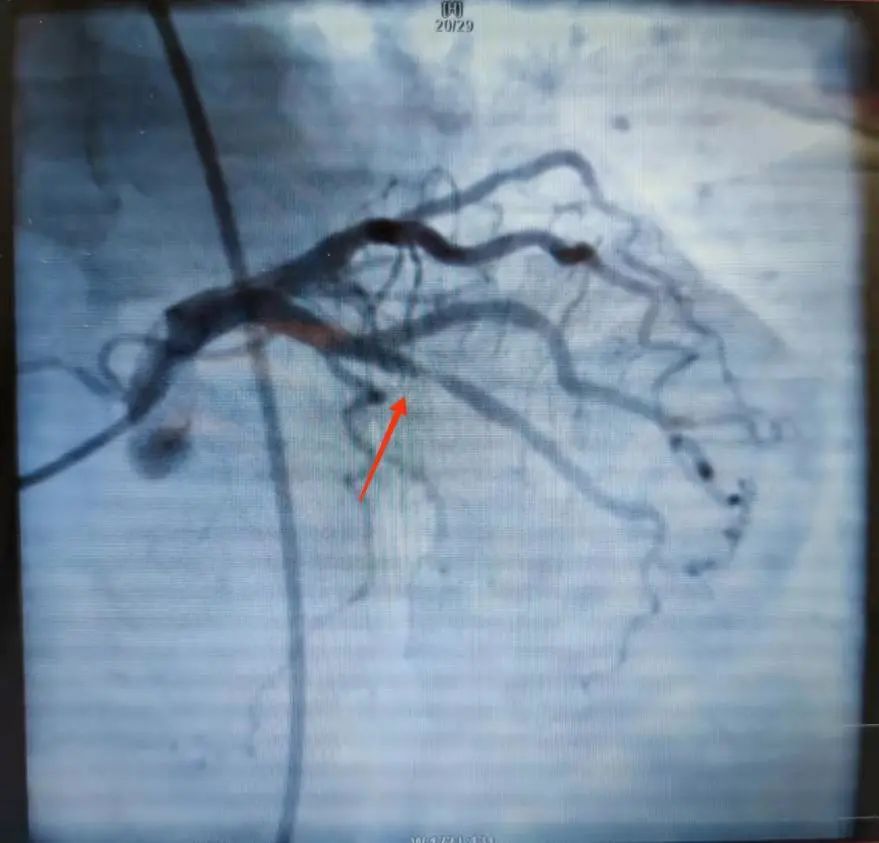

近日,北京燕化医院心内科在为一名心绞痛患者进行冠脉造影检查后提示,患者最严重的病变在回旋支中段,狭窄约75-80%,属冠状动脉临界病变。以往这种情况,是否需要植入支架,全凭医生根据经验判断。

为进一步评估该患者是否存在心肌缺血,是否需要对其进行植入支架治疗,心内科李钢主任为患者进行了FFR的测量操作,最终为该患者测量的结果为0.94,该结果提示患者心肌缺血的可能性小,遂避免了植入冠脉支架介入治疗,该患者也对继续加强药物治疗的方案非常满意。